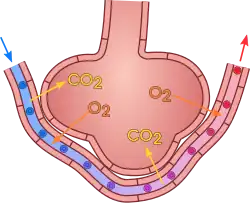

An annotated diagram of the alveolus

The cross section of an alveolus with capillaries is shown. Part of the cross section is magnified to show diffusion of oxygen gas and carbon dioxide through type I cells and capillary cells.

Gas exchange in the alveolus

Type I cells are the larger of the two cell types; they are thin, flat epithelial lining cells (membranous pneumocytes), that form the structure of the alveoli.[3] They are squamous (giving more surface area to each cell) and have long cytoplasmic extensions that cover more than 95% of the alveolar surface.[12][17]

Type I cells are involved in the process of gas exchange between the alveoli and blood. These cells are extremely thin – sometimes only 25 nm – the electron microscope was needed to prove that all alveoli are lined with epithelium. This thin lining enables a fast diffusion of gas exchange between the air in the alveoli and the blood in the surrounding capillaries.